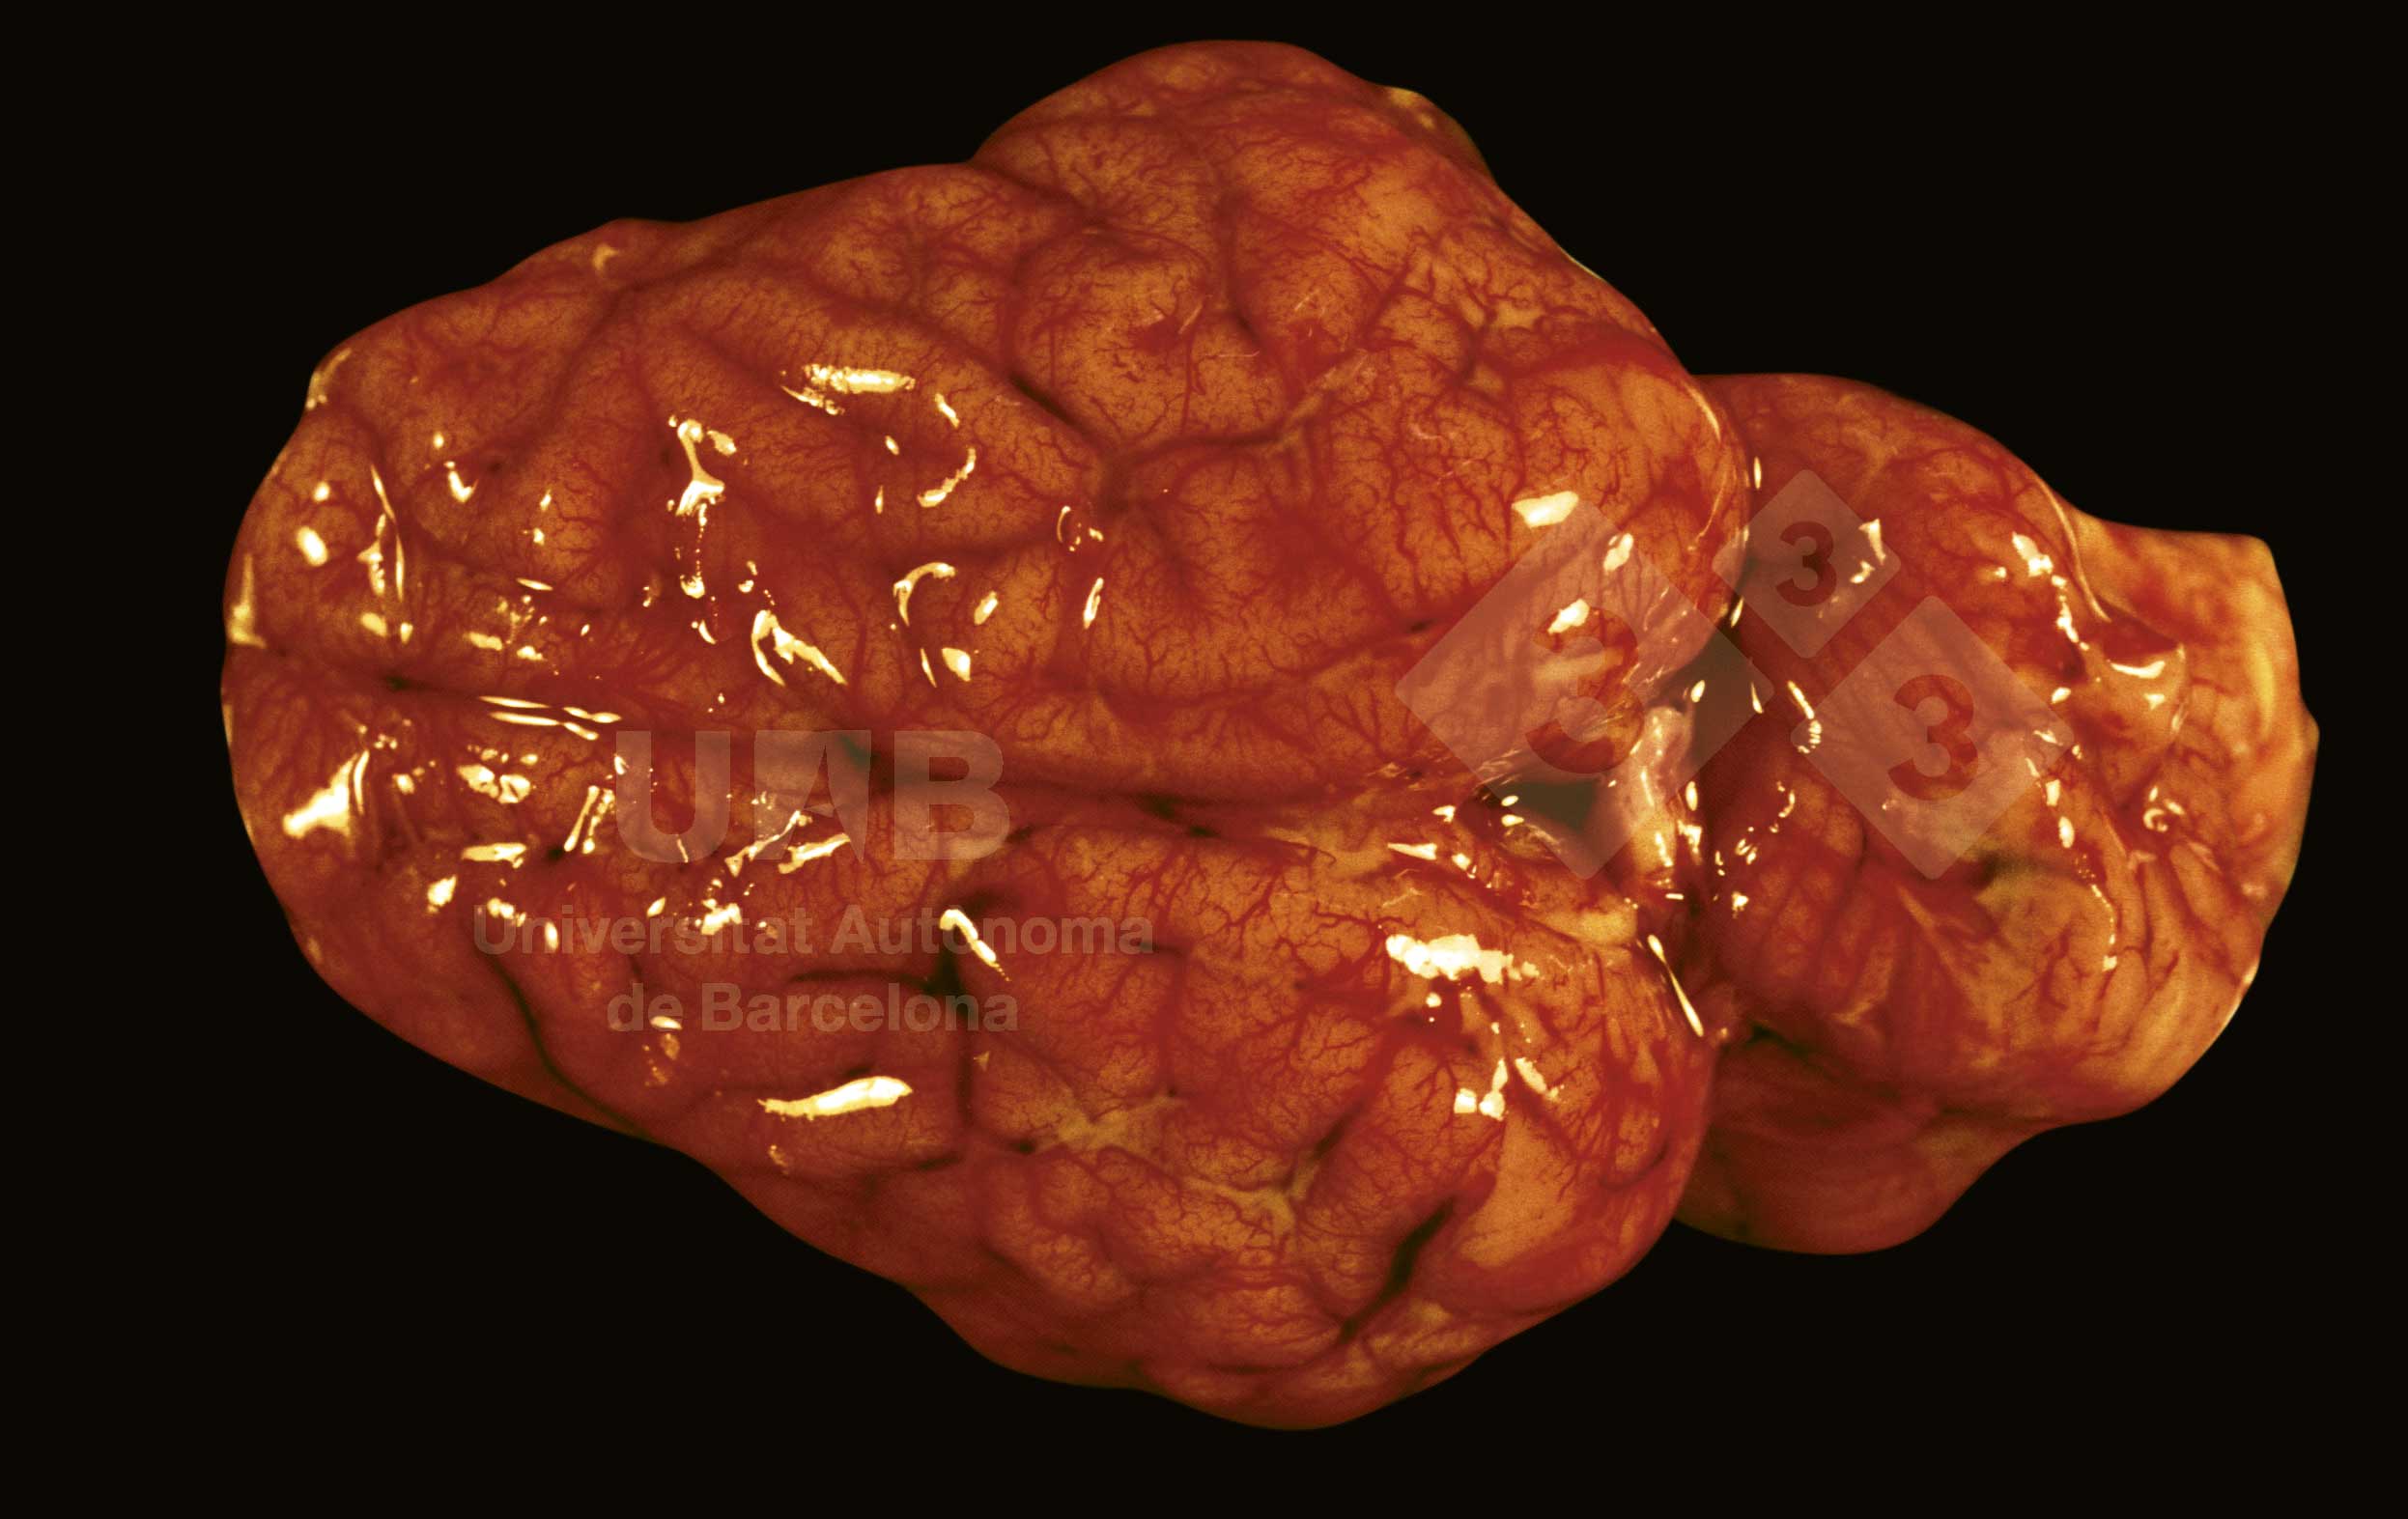

W przebiegu zapalenia opon mózgowych obserwuje się występowanie zatorów. Czasem, jak i w tym przypadku, widoczne są rozsiane ogniska wysięku fibrynowego, w bruzdach. U podłoża zapalenia opon mózgowych leżą zakażenia: Streptococcus suis, Haemophilus parasuis and Escherichia coli i inne.